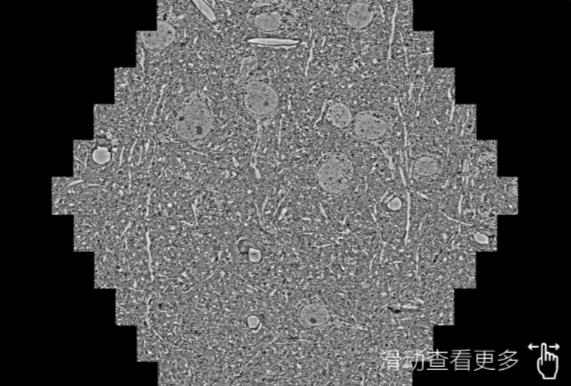

鼠脑切片。左图使用嘉定蔡司嘉定扫描电镜MultiSEM706对165μmx143pm面积区域成像,耗时仅需1.5秒。右图为鼠脑切片中30μm区域放大效果。样品由芝加哥大学B.Kasthuri提供。

使用蔡司高速嘉定扫描电镜MultiSEM对1mm²人脑皮层组织进行高分辨成像,并对其中的各种细胞结构进行三维重构分析。左图展示了2x3mm²组织平面中锥体神经元的三维重构效果。右图显示了局部体积神经元三维重构。图像由哈佛大学chtman实验室提供,渲染图由D. Berger 制作。